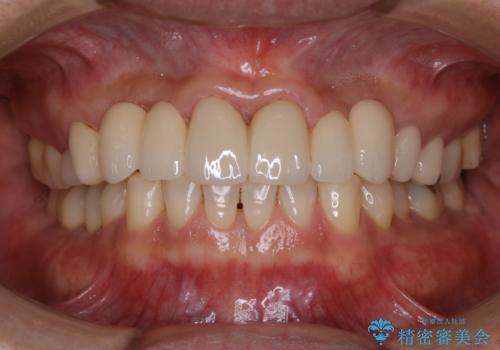

歯石や着色、古くから蓄積した汚れは日常の歯ブラシではとることが出来ません。

歯科医院にて専門的に行うクリーニング(PMTC)を定期的に行うことがとても重要です。

むし歯がなく歯が痛くならない限り歯科医院へ来院する機会がないと、知らぬ間に歯周病などが進行してしまう場合があります。そのため痛みがなくても定期的に歯科医院に来院しメンテナンスを受けることをお勧めします。